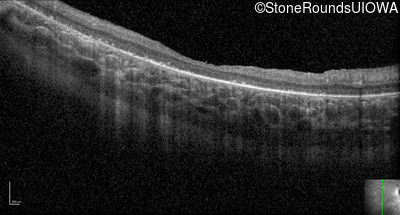

Optical Coherence Tomography - Left - 20/80

Exemplar / OCT Stack